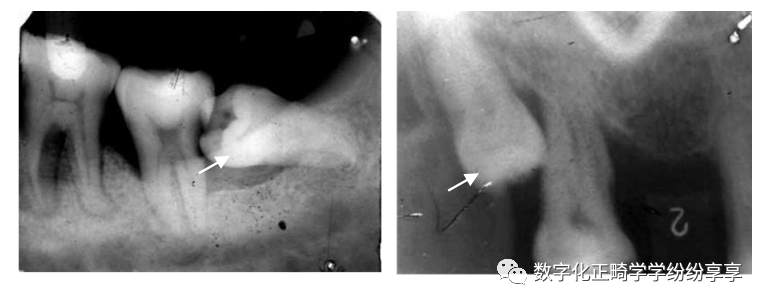

埋伏牙

曲面断层片怎么看正畸【曲面断层片(全景片)】如何解读和查看:牙周?牙体?牙髓?关节?_https://www.jmylbn.com_新闻资讯_第2张

阻生牙

曲面断层片怎么看正畸【曲面断层片(全景片)】如何解读和查看:牙周?牙体?牙髓?关节?_https://www.jmylbn.com_新闻资讯_第19张

拍片注意:阻生牙位臵、方向、本身情况、与邻牙关系、数目及形态、与下牙槽神经管距离和磨牙后间隙大小等。